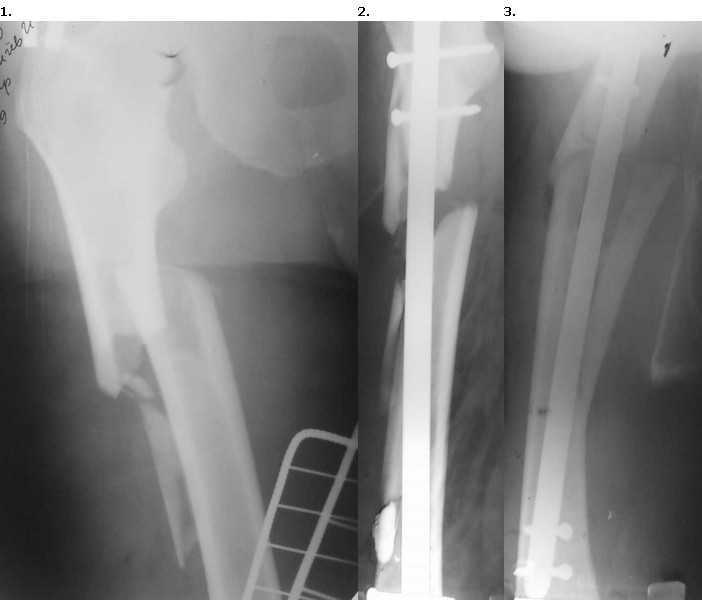

Доброго времени суток, уважаемые коллеги.Пациент 56 лет поступил в отделение 28.12.09 со свежим переломом в/3 правого бедра. 15.01.10 произведен закрытый БИОС гвоздем Sanatmetal.

(d13мм), во время которого произошло раскалывание проксимального и дистального отломков. ЭОПа в больнице нет, для определения локализации направителя пользовались стареньким "Арманом". После заведения гвоздя по проводнику снимки на столе больше не делали, дистальное блокирование оч.быстро с использованием электромагнитной навигации. В послеоперационном периоде выраженные боли и отек. На контрольных рентгенограммах вот такая картина.

После посмотрели за экраном - гвоздь стоит стабильно как в проксимальном, так и в дистальном отломке,но контакта между проксимальным и дистальным нет. Вопросы:

Судя по рентгенограмме бедра в боковой проекции, гвоздь в дистальном отломке заведен неправильно (упирается в передний кортикал), а в прямой проекции довольно солидный диастаз между отломками. Учитывая эти два фактора, можно предположить, что с началом нагрузки на конечность стержень может перфорировать дистальный отломок и приведет к дальнейшему угловому смещению отломков, которое уже имеет место первоначально. Мое мнение: перепровести гвоздь с заданным направлением к центру метафиза, тем более, что у пациента выраженный болевой синдром скорее всего связанный с вышеуказанными причинами. С уважением Нурмет Магомедович, г.Тюмень